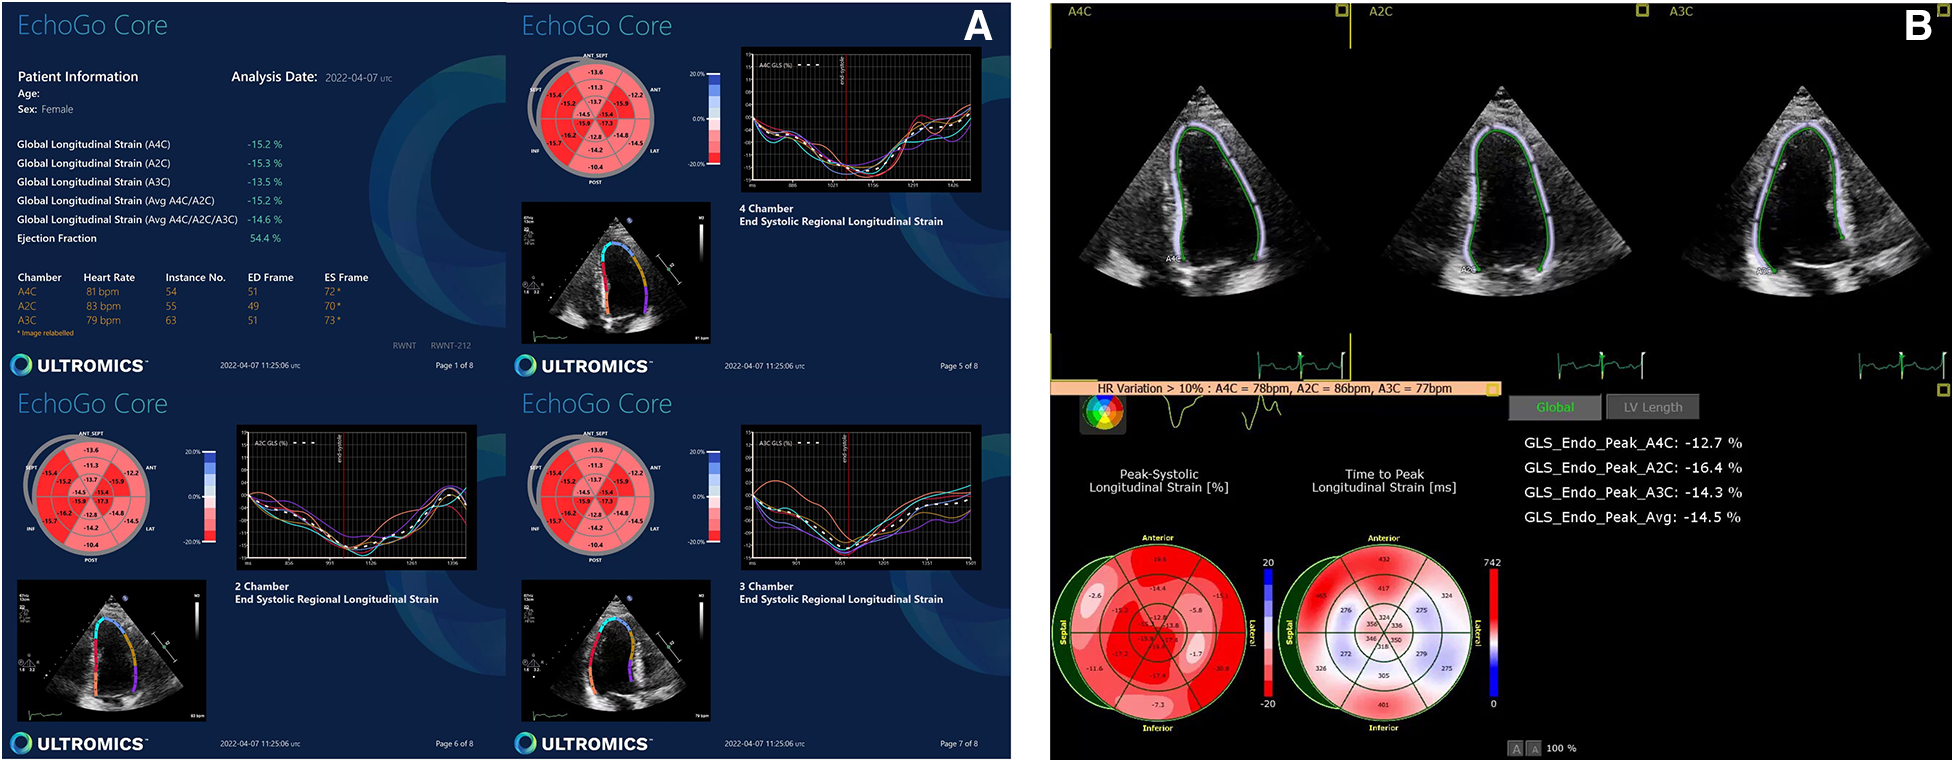

AI-generated GLS and LVEF values were acquired in 14% and 51% of all studies, respectively. Representative examples of normal and abnormal GLS studies analysed by AI-generated and conventional assessment are shown in Figures 1, 2 respectively. The rate of success in obtaining strain results using AI vs. conventional methods for the three standard apical views were: A4C, 56% vs. 74%; A3C, 14% vs. 38%; A2C, 46% vs. 53%, respectively (Figure 3).

Figure 1

Normal GLS data yielded by (A) AI-based and (B) conventional semi-automated strain analysis.